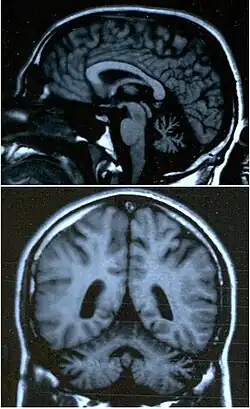

Images IRM cérébrales d'un jeune patient âgé de 25 ans, montrant une atrophie cérébelleuse.